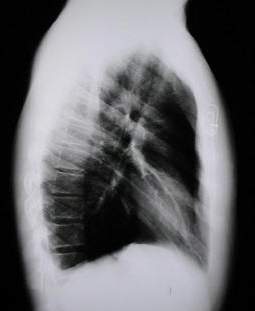

Radiología del Tórax

En la proyección lateral Izquierda (imagen de abajo a la derecha) se aprecia la protrusión esternal y en dirección anterior hasta la unión del tercio medio con el inferior, la retracción del xifoides, insinuando la estrechez de la base del tórax (Tórax en barril), el amplio diámetro anteroposterior del tórax se reduce en su extremo inferior.

Rx. Tórax Lateral Izquierda